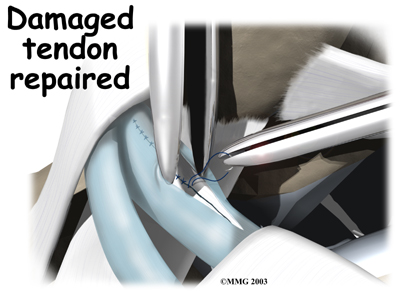

Tendon Repair

Tendonosis may require repair if a preoneal tendon is split down its length. This type of tear mainly affects the peroneus brevis. The surgeon fixes this problem by first around the tendons. If the split is smaller than one-third the width of the tendon, the torn portion may simply be removed. Larger splits are sutured along the length of the tendon. The tendon sheath is , and the skin is closed with sutures.